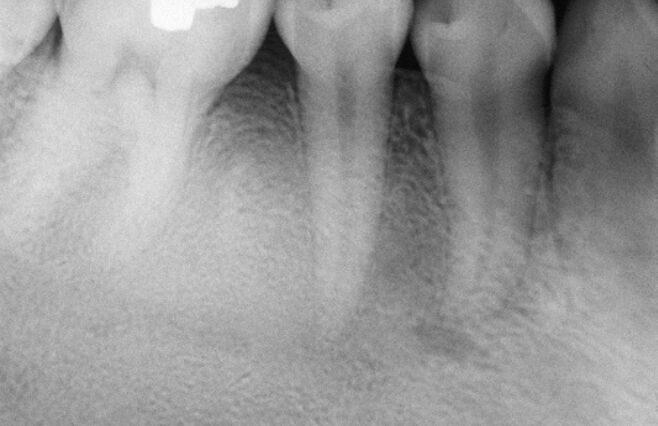

65.附圖影像中箭頭所指之處,為下列何種構造? (A)鼻腭管(nasopalatine duct) (B)前鼻棘(anterior nasal spine) (C)上顎間縫(intermaxillary suture) (D)營養管(nutrient canal)

66.附圖中紅色箭頭所指放射線透過性線條(radiolucent lines)為下列何者? (A)mandibular canals (B)nutrient canals (C)lamina dura (D)lingual foramen